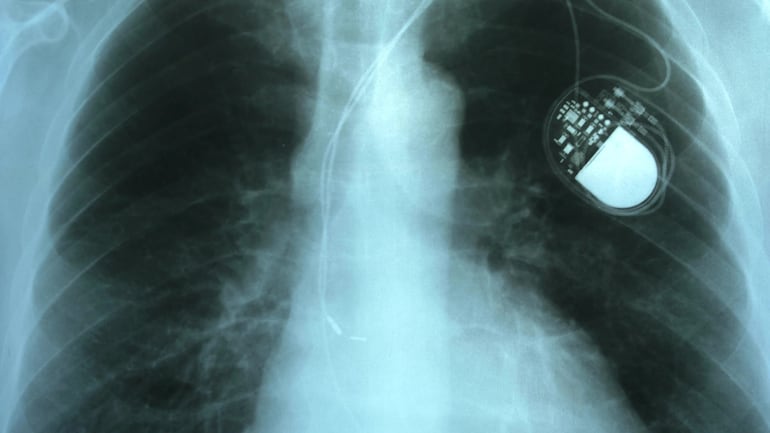

Cuando ese circuito se enlentece o se interrumpe, puede aparecer bradicardia (pulso demasiado lento) o bloqueo AV (la señal no baja bien a los ventrículos). Ahí entra el marcapasos: un dispositivo implantable compuesto por un generador (batería y microelectrónica) y uno o más cables/electrodos que se ubican en el corazón.

Su lógica es simple y sofisticada a la vez: detecta la actividad eléctrica propia y, si advierte pausas o un ritmo por debajo de un umbral programado, emite un impulso para disparar el latido.